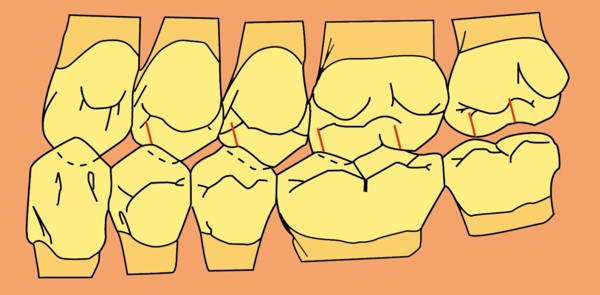

RESUMEN Más allá en el tiempo, respecto de las razones más frecuentes de fracasos como temperatura de fresado, infecciones, falta de fijación inicial, falta de higiene, etc., la OCLUSIÓN recibe sobre sí, la responsabilidad de la permanencia de la osteointegración, como así de la ortofunción del sistema todo. Sometimes ago,conserning the most frecuent reason of failures such as the strawberry action temperature, infections and lack of hygiene…etc.,the OCLUSION has itself the responsability af having the osteointegration well as the allsistem ortofunction . DESARROLLO La valoración de los fracasos en IMPLANTOLOGÍA es difícil de contabilizar sobre todo después del año, ya que el confort logrado por lo general, hace que el paciente realice correctamente sus primeros controles, y después; apoyado en su bienestar; intente subconscientemente olvidar ese período de su vida, que si bien le devolvió su capacidad masticatoria, fonética, social, etc., le ocasionara gastos, molestias, sufrimientos. … la APLICACIÓN de dichas fuerzas, requiere de una exactitud mucho mayor. Los esquemas propuestos a través de los años, no son muchos ni muy variados… I-Evitar las fuerzas tangenciales. II-Repartir las fuerzas lo máximo posible. Sin embargo, muchas veces se confunden los conceptos anteriores con criterios inexactos. Por ej: a-Reducción de las caras vestibulares y palatinas, aceptando que la menor superficie de intercontactos reduce la carga. b-Utilización de la Función de Grupo Posterior, en la creencia de que repartiendo el esfuerzo en las piezas posteriores, ganamos resistencia; a la potencia ejercida por los músculos. c-No permitiendo el contacto excéntrico de un canino implantado, para aliviarlo de las cargas laterales, sobre cargando de esta manera la tabla premolar-molar en el Lado de Trabajo. Algunos conceptos aislados, que forman parte de toda una filosofía de la Oclusión (OCLUSIÓN ORGÁNICA), sean tal vez de ayuda para echar luz sobre los preceptos anteriores. 1º-PROPORCIONES FUNCIONALES DE UN PAR OCLUSAL En la figura siguiente, observamos la relación final masticatoria de un PAR OCLUSAL: En el se ven los contactos puntiformes, producto del choque de superficies redondeadas contra superficies redondeadas («Solo pueden encontrarse en un punto» Ref: Principios Mecánicos Esferoidales.W.Mc.Horris.) Si Miramos con atención este tipo de contactos interoclusales, veremos que la superficie actuante es mucho menor que la superficie total de la cara oclusal: 45% (Fig.1) Por lo tanto, si no es por razones del Pilar de Emergencia para no crear un espacio biológico inadecuado… ¿POR QUÉ REDUCIR LA CARA OCLUSAL VESTÍBULO LINGUALMENTE? (Figs. 2-3-4-5) Si observamos con atención las figuras 2-3-4-5, veremos desde todos los planos , que el área contactante es muy reducida respecto del ancho oclusal total, siendo las fuerzas resultantes , AXIALES al eje implantario. 2º-FUNCIÓN DE GRUPO POSTERIOR. FUNCIÓN CANINA. Tres son las razones por las cuales nos inclinamos a la utilización de la Función Canina. En cambio, en el esquema de FUNCIÓN CANINA, podemos observar que el BRAZO DE POTENCIA, es prácticamente igual al de RESISTENCIA, equilibrando de esta manera la palanca y destruyendo mucho menos las estructuras de soporte(Interface I-H) (Fig. 7) Otra de las razones de peso en este tema es la DIFERENCIA DE ANGULACIÓN que existe entre la cara palatina del canino y las vertientes contactantes del sector premolar-molar. A MAYOR ANGULACIÓN, MENORES FUERZAS LATERALES(Perpendiculares al Plano), y por lo tanto , menor destrucción de la interface Hueso-Implante(Figs. 9-11). DIFERENCIAS EXCITATORIAS DE LOS GRUPOS MUSCULARES. Por último debemos considerar que el intercontacto dentario del sector anterior, estimula excitatoriamente a las fibras anteriores y verticales del temporal (Figs.12-13-14-15), mientras que los contactos posteriores lo hacen con la cincha pterigo-maseterina(Fig. 16-17-18-19) Por lo tanto ,si se comprende el fisiologismo de estos conceptos, es sencillo entender que la sobrecarga de los sectores posteriores es nocivo generando fuerzas tangenciales de Alto Potencial Patológico. 3º-FUNCIÓN DE GRUPO ANTERIOR Las ventajas de un Brazo de Resistencia mayor se acentúan cuando tenemos el esquema de FUNCIÓN DE GRUPO ANTERIOR. Además, debemos tener en cuenta que, durante la función de un Ciclo Masticatorio, es más importante la Desoclusión Final que la Desoclusión Inicial, ya que al ser más larga esta última, es durante el transcurso de su deslizamiento cuando se ejercen fuerzas laterales mayores(Fig. 21) A medida que la punta del canino inferior se acerca a la O.R.C., o sea al Punto de Contacto Intercanino, las fuerzas laterales disminuyen en virtud del acortamiento del brazo de potencia de la palanca, hasta que, al terminar su recorrido, la fuerza es proyectada axialmente sobre el eje del canino superior, debido a que, al margen de la intensidad que la fuerza trae durante el cierre, la dirección de la misma «apunta» en esa dirección. Por eso decimos que los caninos Axializan el Ciclo Masticatorio. Si estamos imitando en lo posible a la naturaleza, no olvidemos este detalle que los dientes naturales provéen, para evitar las fuerzas laterales del canino a la hora de realizar la supraestructura coronaria del mismo. Es ahora menester acentuar que la problemática concreta se manifiesta, no durante la función, sino durante la PARAFUNCIÓN… Cuando estudiamos recorridos de la Dinámica Mandibular, desde el conocido Bicuspoide de Posselt hasta cualquiera de los registros pantográficos, estamos invirtiendo la dirección del movimiento… A.- El primer premolar es el más anterior de la tabla oclusal posterior. Por lo tanto el brazo de resistencia es el mayor de dicha tabla. B.- El lateral, como parte del grupo anterior, cuenta con un empotramiento tipo «clavo largo», y el interseptum lateral -canino, que se opone a la fuerza, es mucho más grueso que la tabla vestibular del primer premolar(Fig.23) C.- Condiciones, las dos anteriores que se favorecen considerablemente, si al enfundar el lateral se logra junto al central una Función de Grupo Anterior. D.- De manera más artificiosa, la instalación de una placa de relajación, soluciona durante la noche lo nocivo de las fuerzas laterales. Veamos un par de casos, como ejemplo de lo dicho: Paciente de 54 años que se presenta a la consulta portando prótesis completa superior y antagonista natural que soporta fundas de porcelana. Obsérvese la función de grupo posterior ejercida, y las consecuencias de la misma: Otro paciente que presenta fractura de la cúspide fundamental de un onlay de porcelana antagonista de cinco piezas implantadas (Fig.27). Radiográficamente se observa la desinserción de uno de sus abuttments cementados (Fig.28). En el Lado de Trabajo (LT), no existe el canino encargado de desocluir la zona afectada (Figs.29-30) Como corolario, cabe entonces una pregunta: ¿Es el Implante en el canino quien debe preservar de patología oclusal al resto del sistema…. ¿Es el Implante…un medio…o un fín? BIBLIOGRAFÍA 1- Dibujos tomados del libro del mismo autor: «OCLUSIÓN ORGÁNICA… UN CAMINO HACIA LA REHABILITACIÓN ORAL»(en preparación) 2- «NEUROFISIOLOGÍA DE LA OCLUSIÓN» 3- «OCLUSIÓN Y FUNCIÓN» 4- «FUNDAMENTOS, TÉCNICAS Y CLÍNICA EN REHABILITACIÓN BUCAL» 5- «OCLUSIÓN Y REHABILITACIÓN» 6- «DISFUNCIÓN TEMPOROMANDIBULAR» 7- «PROCEDIMIENTOS CLÍNICOS Y DE LABORATORIO DE OCLUSIÓN ORGÁNICA» 8- «ESTUDIO ELECTRÓNICO DEL MOVIMIENTO MANDIBULAR» 9- «OCLUSIÓN: CONCEPTO PARA EL CLÍNICO» 10- «IMPLANTOLOGÍA CONTEMPORÁNEA» 11- «OCLUSIÓN Y DIAGNÓSTICO EN REHABILITACIÓN ORAL» 12- «PRINCIPIOS DE OCLUSIÓN»

A nivel del canino observaremos alrededor de 70º respecto de la horizontal en sus rebordes marginales, que son las áreas funcionales , y un ligero aumento de la misma a nivel de la fosa palatina(Fig.8).

Las piezas posteriores presentan de hecho una angulación mucho menor en sus áreas funcionales(Fig. 10)

Cuando se estudia la física del Plano Inclinado se observa que a medida que este se aleja de 0º acercándose a 90º,su DESLIZAMIENTO aumenta, en detrimento de su ROZAMIENTO, es decir: